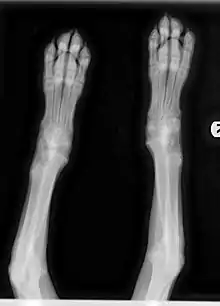

Radiographic Features

Diagnosis relies on clinical signs and characteristic changes in radiographic images of the metaphyses. Bone changes can be observed on radiograph, and the disorder may progress to actual angular limb deformity. In the early stage of the illness, the metaphyseal area on X-ray may be observed to have an uneven radiolucent zone parallel to the physis with a thin band of increased radiodensity directly bordering the physis. Early stage radiographic changes have sometimes been described as having a "moth-eaten" appearance (see Figure 3). As the disease progresses, the radiolucent line may disappear and radiodensity may increase in the affected area as the body attempts to repair damage. Relapses can cause new radiolucent lines. This area is often followed by a dark line at the metaphysis, which may progress to new bone growth on the outside of that area. This area represents microfractures in the metaphysis and bone proliferation to bridge the defect in the periosteum.[7]